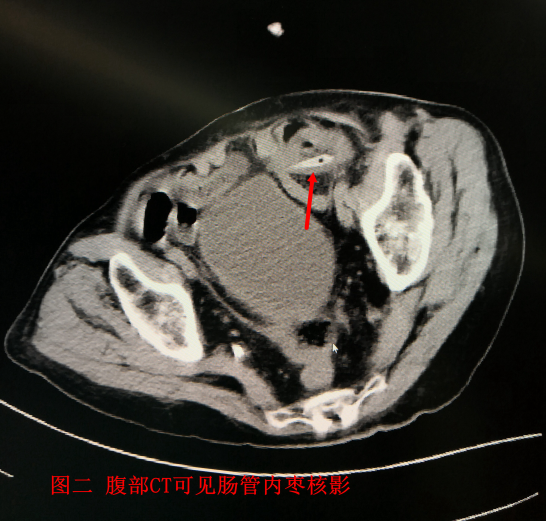

患者韩##,女,93岁,既往冠心病、高血压病史25年余,长期口服药物治疗。患者入院前1天无明显诱因出现下腹部疼痛,为持续性绞痛,阵发性加重,伴有腹胀、恶心、呕吐、停止排气排便。就诊于外院输液治疗后症状未见明显好转。进一步就诊于我院急诊。患者腹部较剧烈,腹部体征相对较轻,完善腹部增强CT后除外肠系膜血管疾病(肠卒中)可能。发现左下腹小肠腹内疝(见图5,并发肠坏死可能。如不急诊行手术可能会发生严重的腹腔感染,危及患者生命。但患者93岁的超高龄,既往有高血压及冠心病等内科疾病,围手术期发生心、脑血管意外及并发心肺肾等功能障碍等风险较年轻患者明显升高。充分向家属交待相关风险,患者家属表示理解。在麻醉科、重症医学科等相关科室的密切配合下当晚急诊行手术治疗。为了进一步明确诊断,行腹腔镜探查,探查见腹腔内大量血性腹水。距左下腹可见局部小肠坏疽缺血水肿(见图6),可见肠系膜根部束带压迫,肠绞窄诊断明确。决定行开腹探查,见距回盲部约40cm处可见部分小肠疝入乙状结肠系膜破损处,疝入小肠约30cm,肠管局部颜色发黑坏死,剪刀剪断肠系膜根部束带及周围粘连,松解疝环。将疝入小肠放回腹腔,温盐水浸泡小肠20分钟,观察局部坏死小肠颜色未见恢复,未见肠蠕动,未触及肠系膜血管搏动。行局部肠管切除(见图7),回肠-回肠顺蠕动侧侧吻合。术后患者入SICU恢复平稳后转回普通病房进一步诊治。给予抗感染、营养支持等治疗。术后患者恢复良好出院。